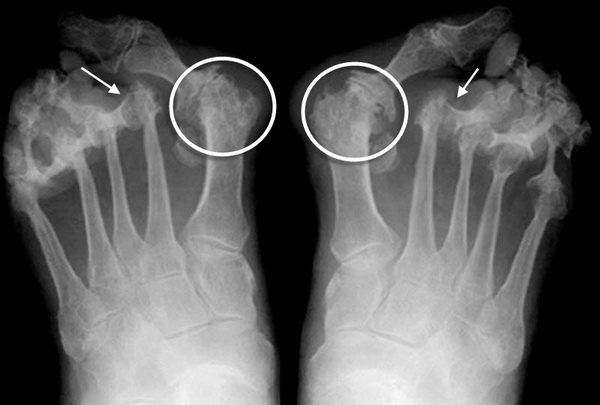

Рентгенологические признаки остеартроза.

- Склероз и кисты в прилежащей к хрящу кости;

- Краевые костные разрастания (остеофиты);

- Уменьшение и деформация суставной щели;

Лабораторных исследований, указывающих на остеоартроз, не существует. Общий, биохимический и серологический анализы нужны для дифференциальной диагностики с другими заболеваниямисуставов.

Методы диагностики

Клинические проявления – не единственные показатели деформации плюснефалангового сустава первого пальца ноги. Стадию заболевания помогают выявить: рентгеновский снимок, МРТ (магнитно-резонансная томография), КТ (компьютерная томография) либо врач назначает пациенту УЗИ. Из всех практикуемых методов диагностики чаще других используется рентгенография, с ее помощью удается точно выявить степень протекания заболевания. Для установления диагноза, кроме анализа результатов лучевого исследования, анамнеза врач обращает внимание на ощущения при пальпации сустава.

- на рентгене можно увидеть уменьшение в размере суставной щели, костные наросты;